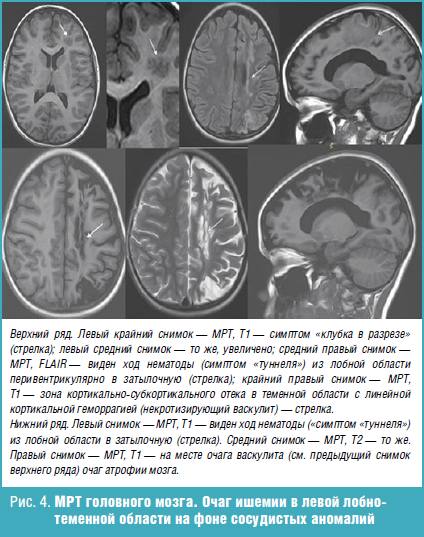

Глиоз левой теменной доли

Глиоз левой теменной доли 109 фото